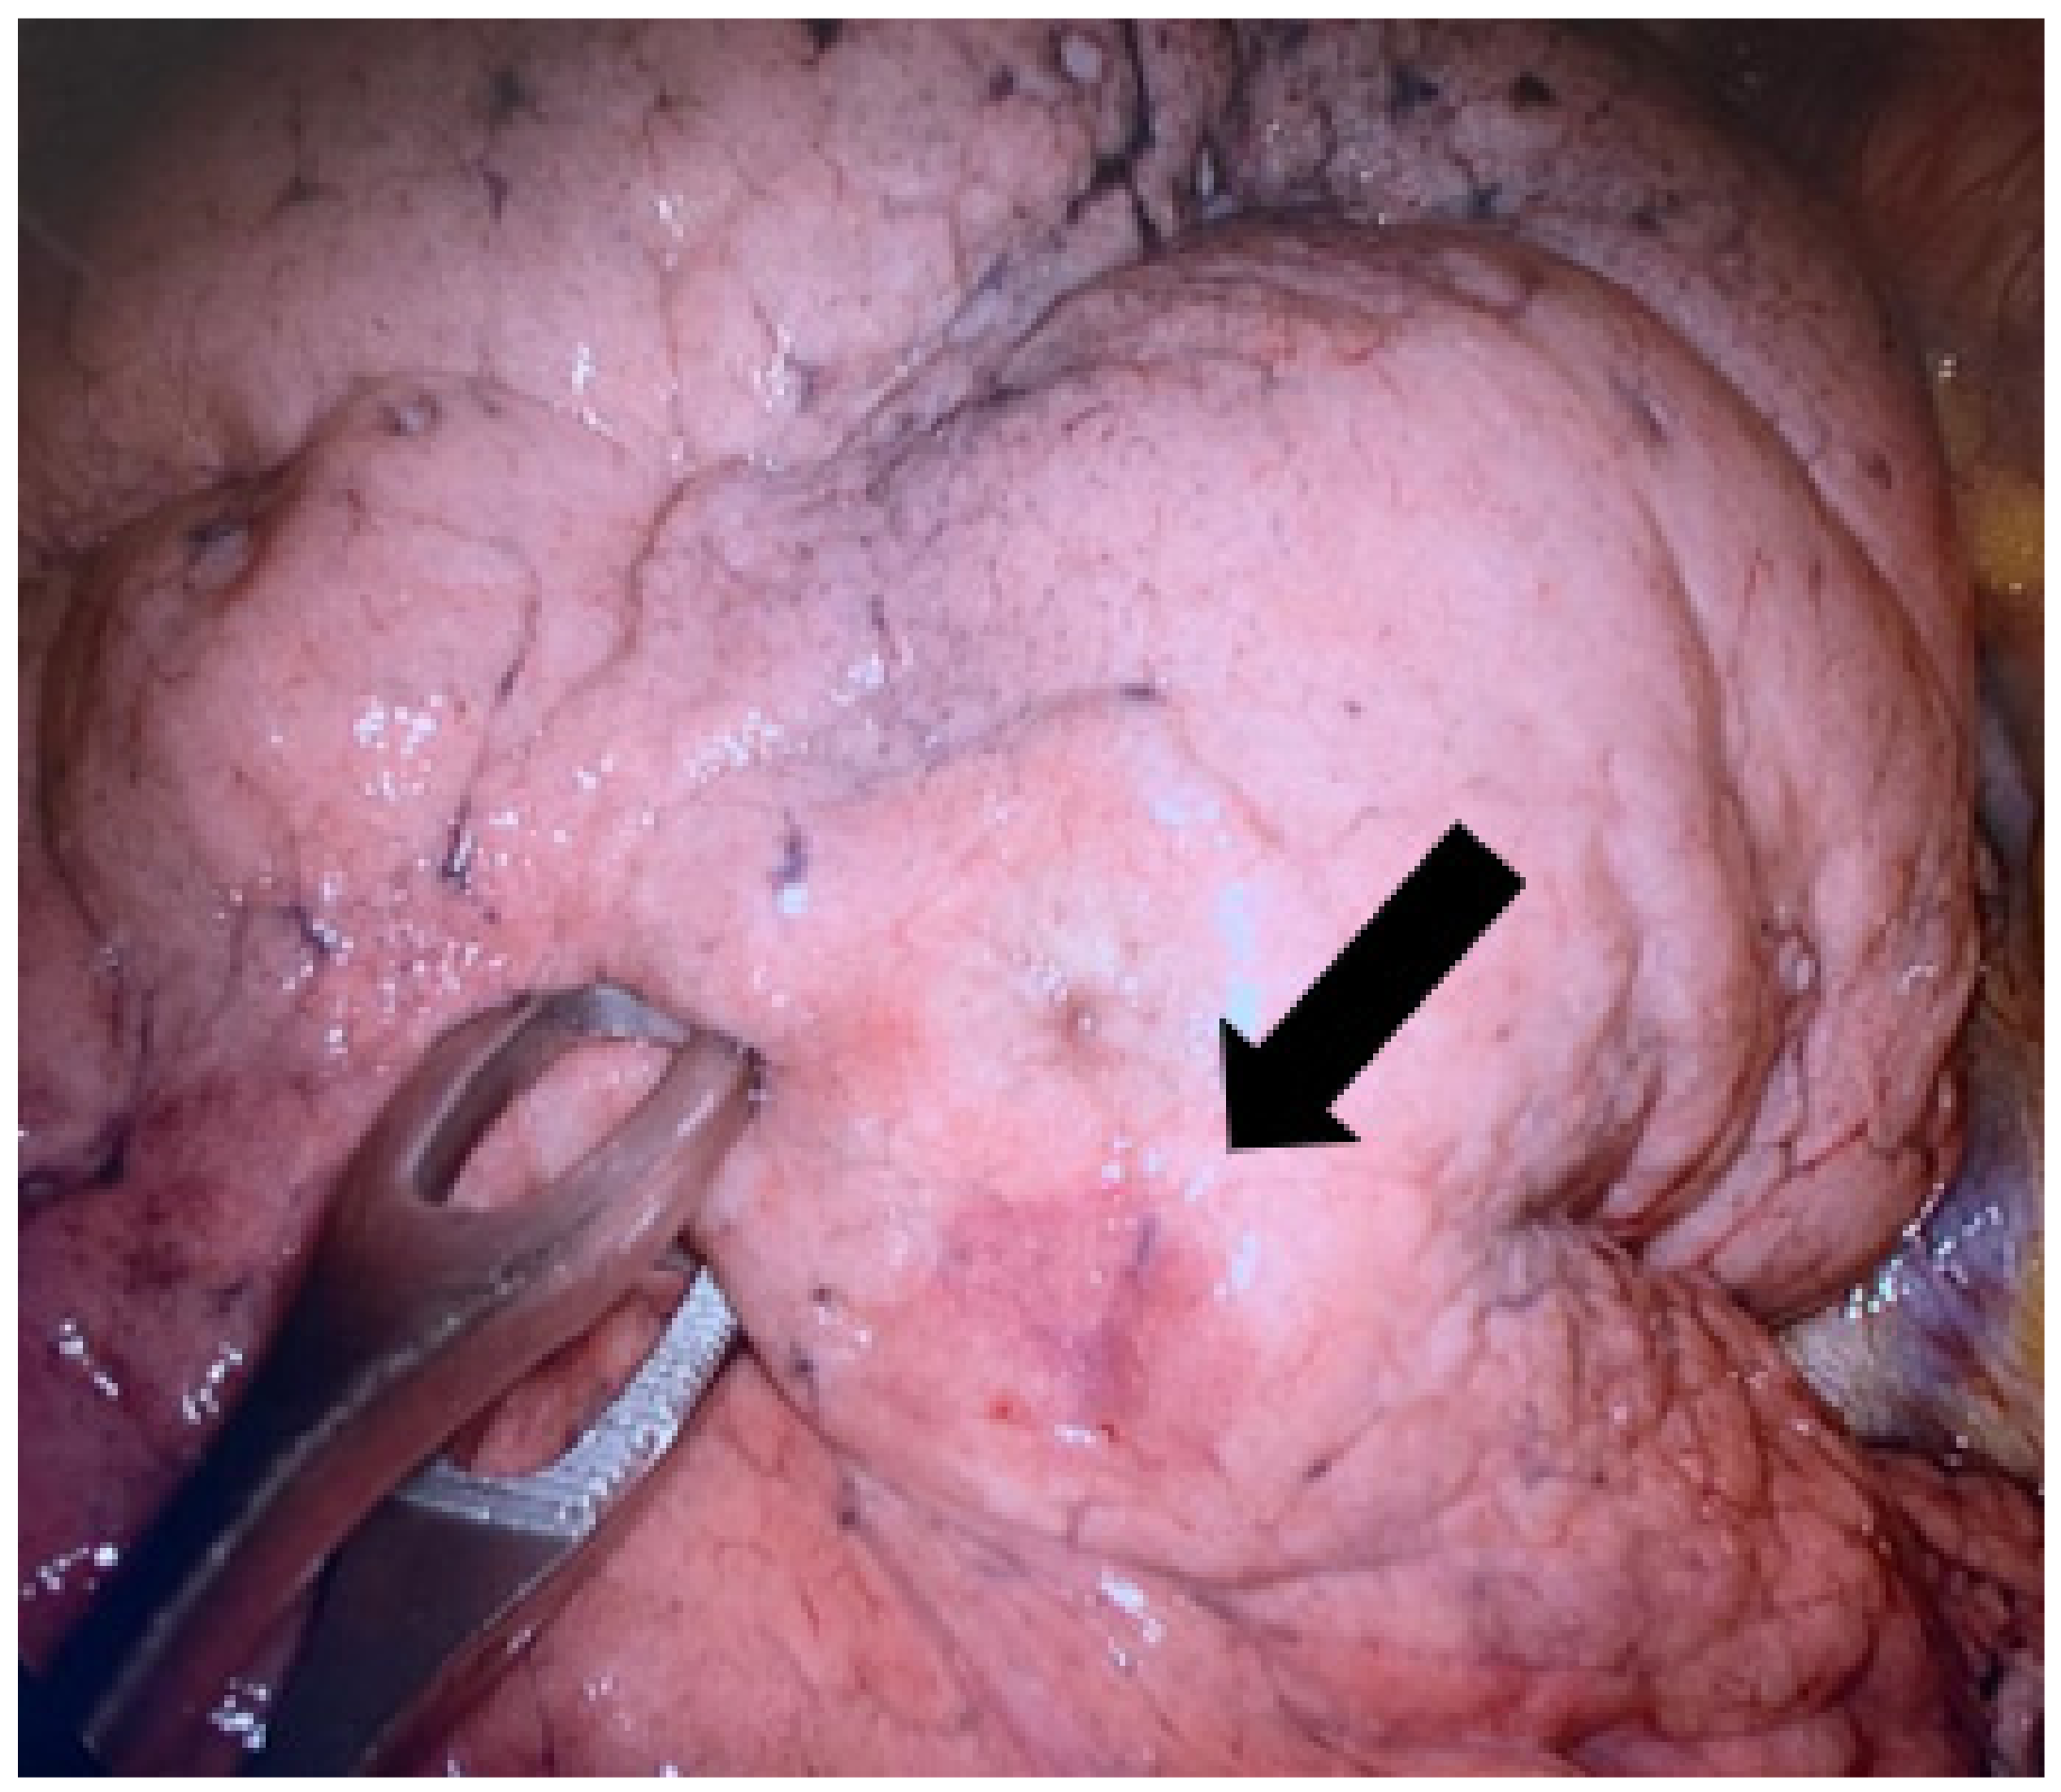

The marking procedure allowed the surgeons to intra-operatively correctly identify the nodule in 54 cases (87.1%), and this resulted in effective resections of the target lesions. In seven cases (11.2%), the plug was displaced in the nearby pleural space. For these patients, the visualization of the parietal/visceral pleural puncture site allowed us to localize the target lesion (Figure 4). One case (1.7%) of a right upper lobe GGO resulted in a non-diagnostic lung excision.

Figure 4. A case of hydrogel plug dislodgment. The arrow indicates the subpleural suffusion nearby the percutaneous lung puncture. Arrow: outlines the subpleural suffusion.